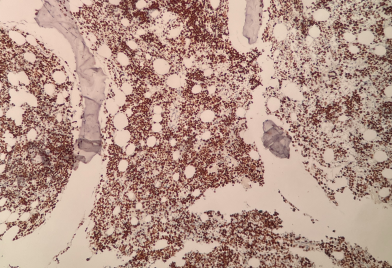

在多项核心诊断指标的染色测试中,其表现呈现出显著优势:

PMS2

MLH1

HER2

CD34

Ki67